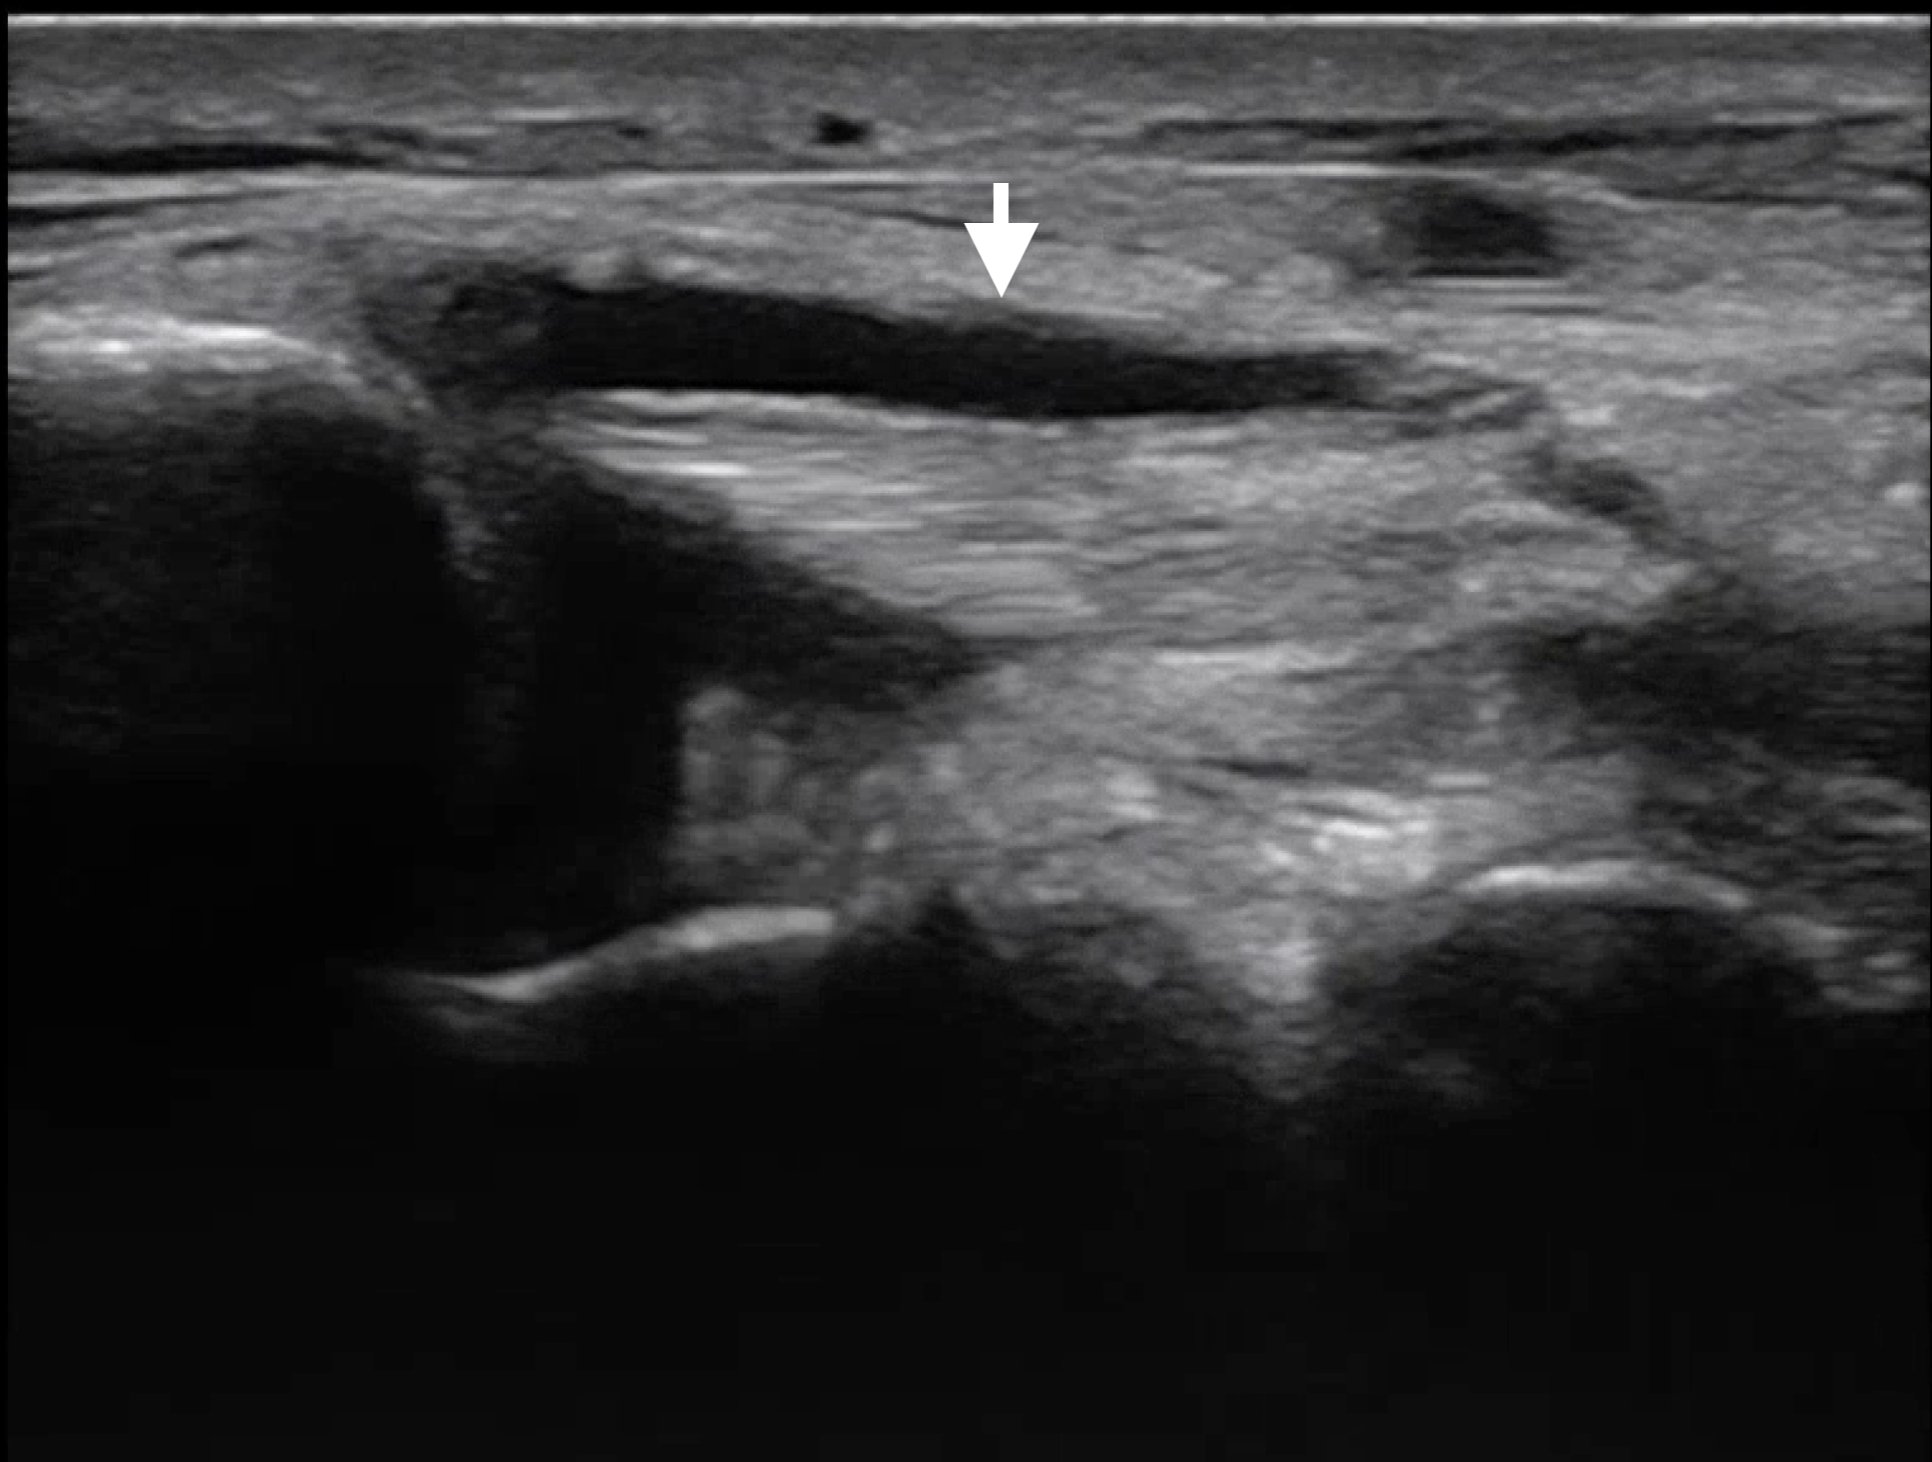

POCUS reveals complete retinal detachment and posterior lens dislocation (arrow) in the affected eye.

Lens dislocation on ultrasound

• Subluxation is characterized by deviation of one side of the lens where it has separated from the iris

• In complete dislocation, the lens can be found within the posterior chamber or vitreous body moving freely with eye movements

• Dislocation into the anterior chamber is also possible

• Ocular ultrasound is highly accurate for diagnosing lens dislocation, with a sensitivity of 96.8% and specificity of 99.4% compared to CT imaging